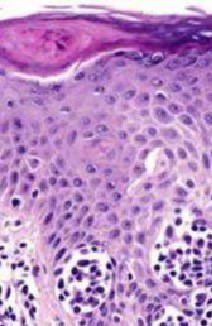

LICHEN PLANUS (LP)

LP DDx

Differential Diagnosis